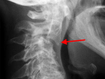

Schmerzsyndrome der Wirbelsäule; Bandscheibenvorfall; Verschleiß der Bandscheiben; Spinalkanalstenose (Verengung des Wirbelkanals); Instabilitäten; Spondylolisthesis (Wirbelgleiten), Myelopathie (Schädigung des Rückenmarkes); Querschnittslähmung; Erkrankungen bei Kinder und Heranwachsenden (z. B. Formveränderungen, Skoliosen, Kyphosen, angeborene Wachstumsstörungen, Verletzungen, Entzündungen, Tumore und Metastasen); Verletzungen des Rückenmarks; Wirbelkörperbrüche; Deformitäten (Formveränderungen, Skoliose, Kyphose); Tumore und Metastasen; Infektionen; Spondylodiszitis (Infektion von Bandscheiben und Wirbelkörper); rheumatische Instabilitäten der Halswirbelsäule sowie zwischen Kopf und Halswirbelsäule; rheumatische Veränderungen der Brust- und Lendenwirbelsäule (z. B. Morbus Bechterew);Verengungen des Foramen magnum; muskulärer Schiefhals; Syndrome durch die erste Rippe; Deformitäten des Thorax (z. B. Trichterbrust, Kielbrust); Erkrankungen und Verletzungen der Rippen; etc.